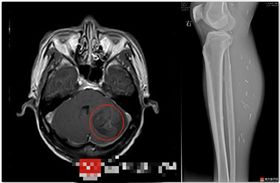

南韓一研究團隊近期發現寄生蟲入侵患者腦部的罕見案例。...

2025/01/01 11:40

吃麻辣鍋癲癇 醫揭元凶:全身7百多條蟲

大陸一名43歲男子日前吃完火鍋,結果突然持續頭痛一陣...